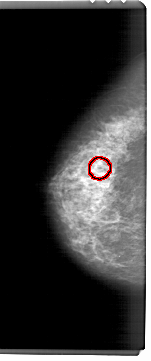

A_1461_1.LEFT_MLO

FILE: A_1461_1.LEFT_MLO.OVERLAY

TOTAL_ABNORMALITIES 1

ABNORMALITY 1

LESION_TYPE CALCIFICATION TYPE AMORPHOUS DISTRIBUTION CLUSTERED

ASSESSMENT 4

SUBTLETY 4

PATHOLOGY BENIGN

TOTAL_OUTLINES 1

BOUNDARY